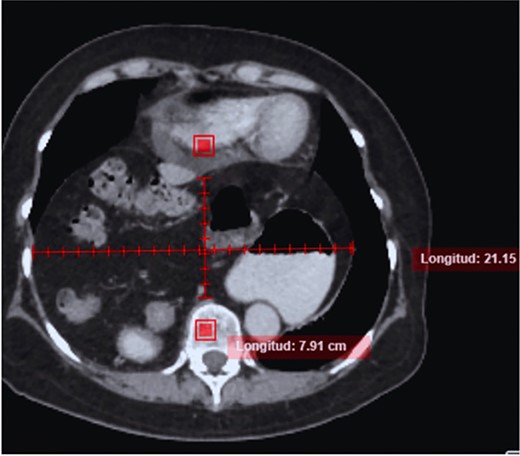

The case is reported of a 52-year-old woman, without significant illnesses, who presented with non-specific chest pain for 1 year, 6 months later with intermittent episodes of dyspnea with great and medium exertion, dysphagia, and heartburn. During the examination, hypoventilated lung fields at the bases, peristaltic sounds, and tympanism on percussion were heard. The thoracoabdominal tomography with contrast shows a diaphragmatic hernia containing the stomach, portions of the duodenum, pancreas, small intestine, and colon (Fig. 1), with a sac measuring up to 20 cm (Fig. 2).

CT in axial section, hernia sac measuring ~21 × 15 × 7 cm is observed.